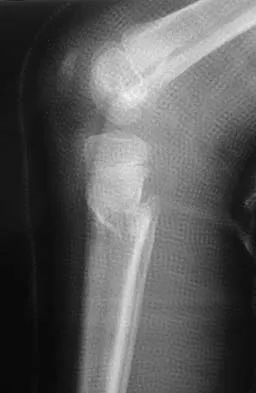

A 78-year-old woman falls onto her nondominant left elbow and sustains the injury shown in Figure 5. What treatment option allows her the shortest recovery time and highest likelihood of good function and range of motion?

Total elbow arthroplasty has become the treatment of choice for complex, comminuted distal humeral fractures in patients older than age 70 years. It yields a faster recovery with more predictable functional outcomes, although limitations of lifting weight of more than 5 pounds must be followed to avoid loosening. Kamineni S, Morrey BF: Distal humeral fractures treated with noncustom total elbow replacement. J Bone Joint Surg Am 2004;86:940-947.